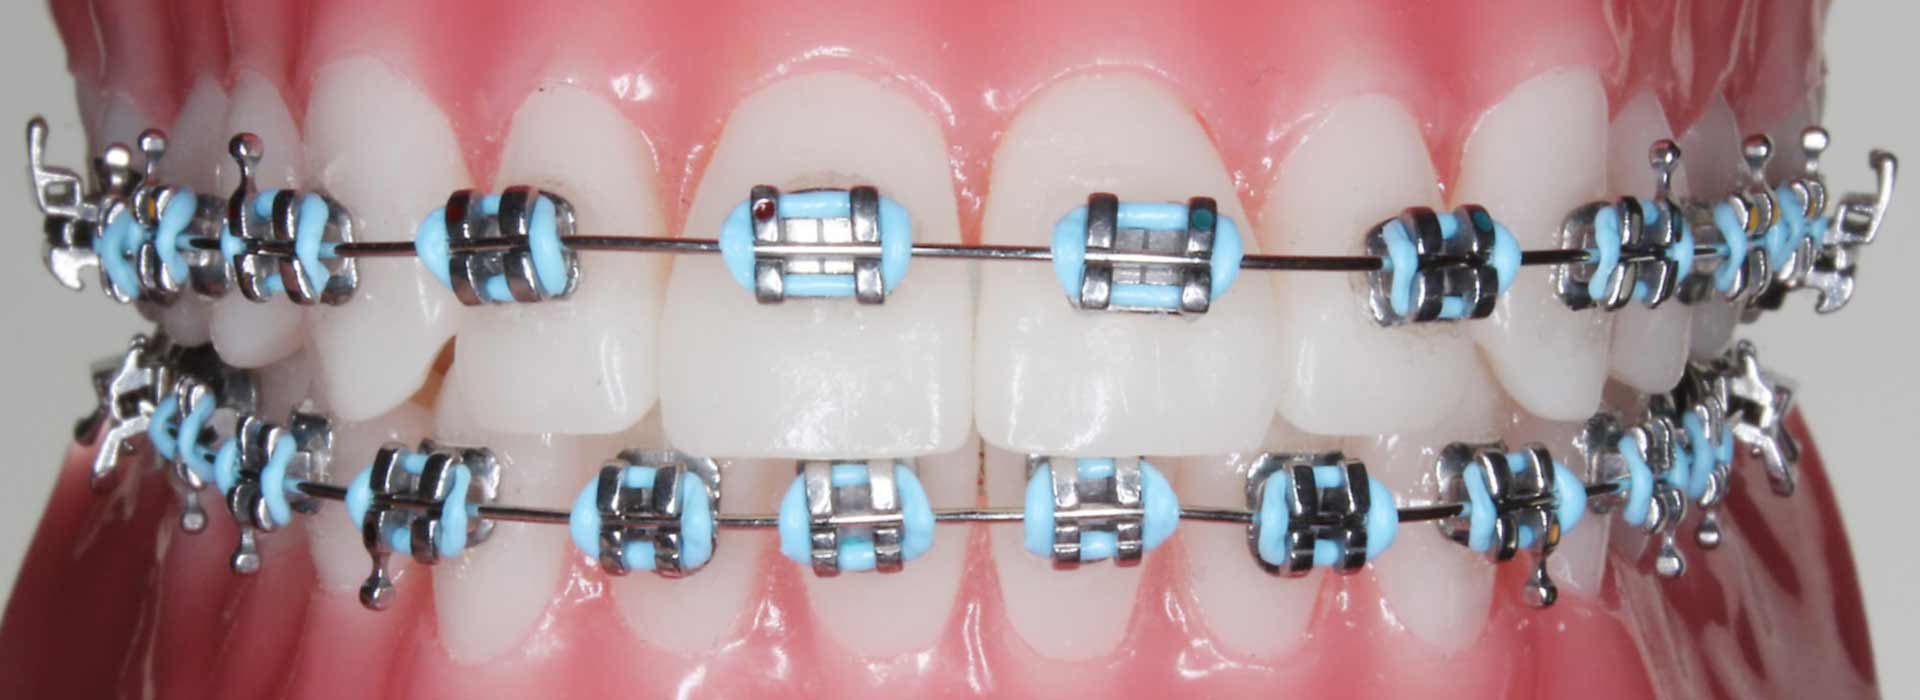

Fixed Braces & TADsتقويم ثابت و TADs

Metal, ceramic or lingual braces with TAD anchorage — the most versatile orthodontic system available.تقويم معدني أو سيراميك أو لساني مع تثبيت TAD — الأكثر تنوعاً في العلاج التقويمي.

Patient Resultsنتائج المرضى

Real Results. Real Patients.نتائج حقيقية. مرضى حقيقيون.